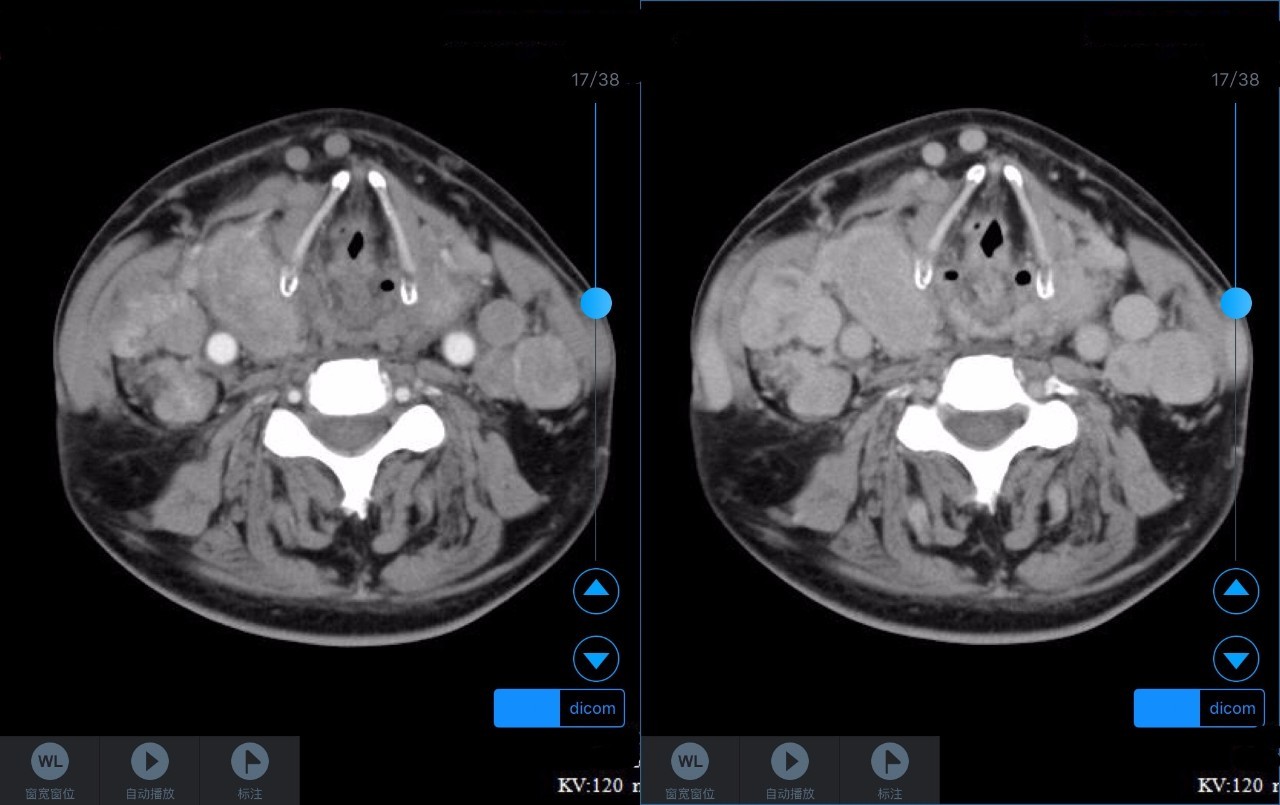

▼患者CT平扫(右)及增强CT(左)检查报告资料

Z主任 甲状腺肿大,内见弥漫多发结节,界限不清,甲状腺包膜毛糙。双侧颈部、锁骨上、纵隔多发肿大淋巴结,病变均强化明显,密度不均,边缘毛糙,考虑甲状腺恶性肿瘤伴多发淋巴结转移,或甲状腺内也是转移瘤。Castleman病多灶者少见,一般病变边缘光整,也不会累及甲状腺。建议穿刺活检。 C主任 双侧甲状腺肿大,密度不均,不均匀强化,甲状软骨未见明显骨质破坏气管右侧壁受压;双侧颈部多发肿大淋巴结,不均匀强化;考虑为甲状腺恶性占位性病变伴双侧颈部淋巴结转移,建议组织学进一步检查。 声明:以上资料均来自和缓名医平台的真实案例,为保护用户隐私,均用化名代替。资深医师Z咨询反馈